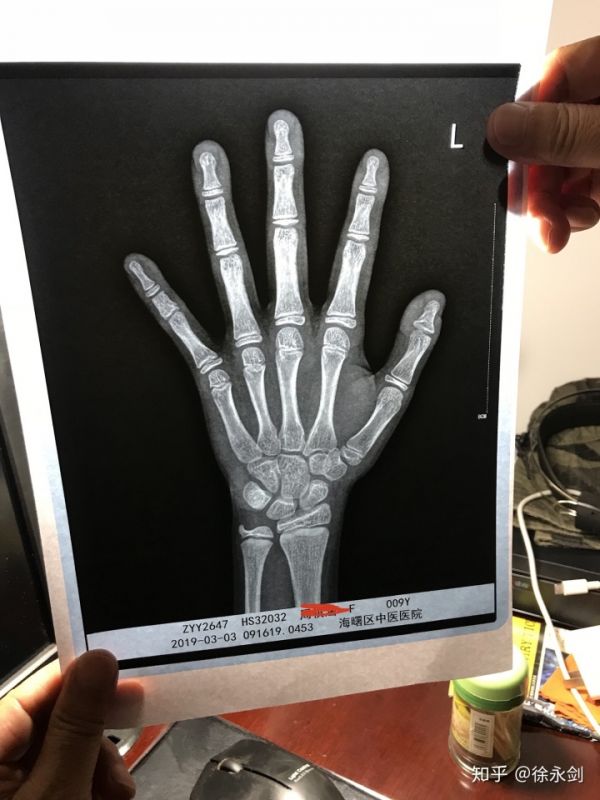

4、骨龄。

是预测成年身高的重要依据。性早熟的孩子一般每三个月或者半年左右复查一次骨龄,骨龄对判断月经是否早来以及预测成年身高是否矮小相当关键,也是临床上决定性早熟的孩子是否需要打针干预的重要参考指标。建议使用中华05标准鉴定数据,预测未来身高数据比较可靠,门诊临床上使用图谱法容易导致数据偏大。